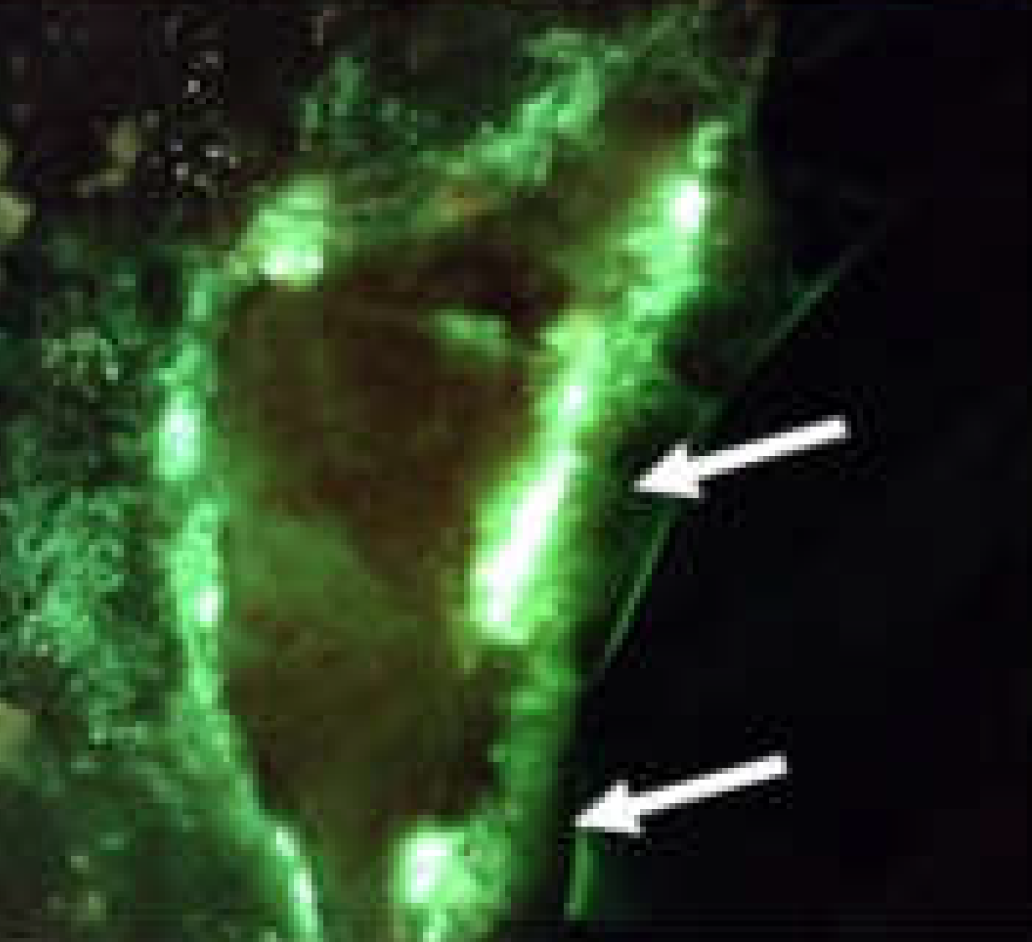

Fluorescence imaging guided dressing change frequency during negative pressure wound therapy: a case series

Raizman, R J. Wound Care 2019